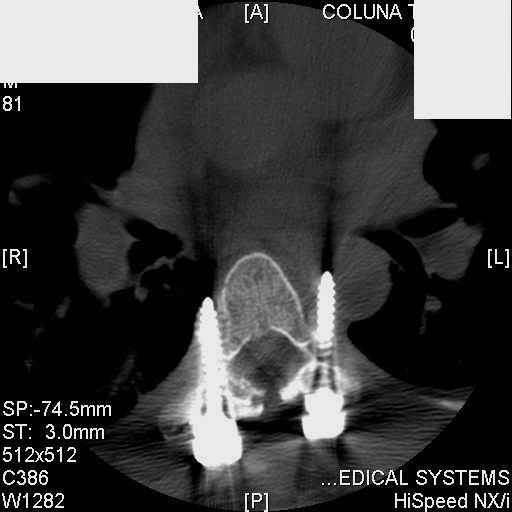

Interesting case. Findings on CT: all four pedicle screws have been placed improperly inthat they miss the vertebral bodies. In addition, the screws on the left side are impingingon the decending thoracic aorta. What I do NOT know is the nature of the original injury, orwhether or not that injury has resolved. I would recommend removal of the hardware. I don'tthink it's a good idea to leave those screws where they are. If the original fracture ishealed, nothing else needs to be done.

dear Mark, all the details are not yet available but the patient is coming to see us foradvice. We probably will see him in the early new year. i thought that the 4th picture showedthe screw to enter the aorta? He is a victim of a motor vehicle crash and thoracic vertebralfracture which appears healed. He was posteriorly decompressed and this device inserted. asyou say there isno evidenece that any of the fixation enters the bodies via the pediclesistead they have passed thru and their end are no where near where they ought to be. If I amcorrect (I would prefer not to be) the aortic intima has been breached by the screw. When thetime comes to take the screw out I thought we should have control of the aorta.What do you think?

Mark Thank you. He is scheduled for a angio prior to transfer here. I keep going back to lookat that fourth image and although it is tough to believe the wall of the aorta seems toencompass the distal 1/2 of the screw. I have come to anticipate mal postion of screws thathave been inserted in hospitals that perhaps may not have the highest quality of equipment,including the human and radiological components. That having been said this case seems tosurpass the usual... one screw out of place or screwed into a disc etc. BTW I am notsuggesting that the screw was placed directly into the aorta but that moviment, pulse actionetc may have caused it to transgress the normal anatomical bounds without evident hemorrhage.